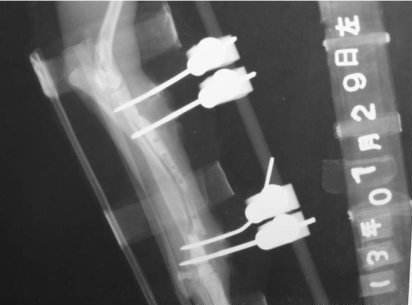

不僅如此,我公司的產(chǎn)品研發(fā)部對我們自己生產(chǎn)的PEEK碳纖維骨外固定器零部件進行了對比性實驗,證明碳纖維增強PEEK復(fù)合材料具有極其優(yōu)越的X射線穿透能力,這對骨外科病人來說意義重大。因為臨床醫(yī)生不僅需要借助X射線對骨折斷端進行修復(fù)或固定手術(shù)操作,還需要經(jīng)常檢查病人的骨折愈合情況,在此情況下,將長絲碳纖維增強PEEK復(fù)合材料作為骨外固定器械材料,在骨外科的臨床應(yīng)用中受到了肯定和歡迎。